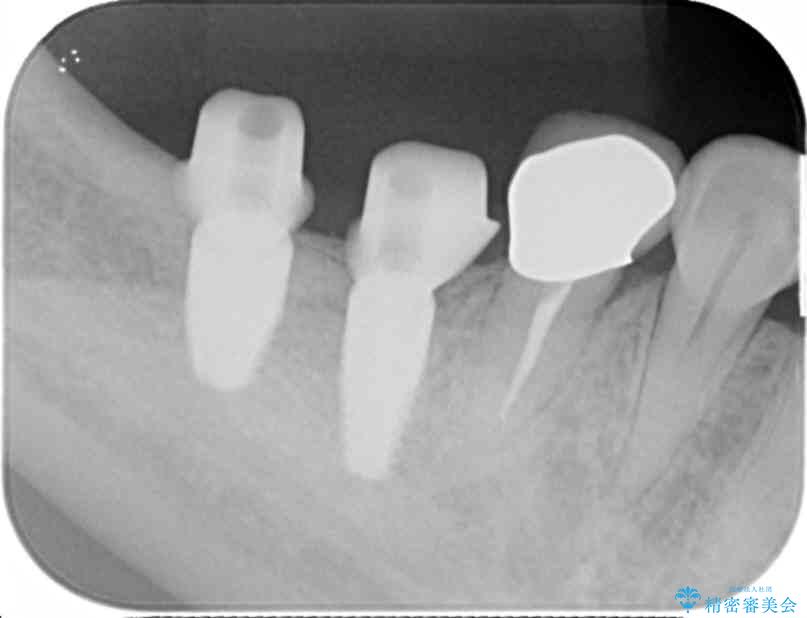

奥歯から膿のにおいがする インプラントによる機能回復 治療前画像 奥歯から膿のにおいがする インプラントによる機能回復 治療前画像 奥歯から膿のにおいがする インプラントによる機能回復 治療前画像 奥歯から膿のにおいがする インプラントによる機能回復 治療前画像 奥歯から膿のにおいがする インプラントによる機能回復 治療前画像 奥歯から膿のにおいがする インプラントによる機能回復 治療前画像

精査した結果、奥歯の根は破折しており抜歯を避けられない状況でした。

咬合力が強く、その他の歯の破折も防ぐために奥歯の咬合機能をインプラントを用いて回復する治療計画を立てます。